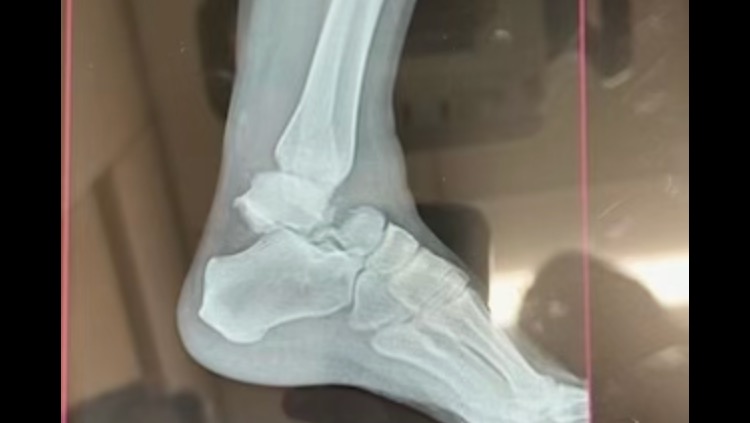

My name is Katherine and I am posting this GoFundMe on behalf of my older sister Mary Rose Cissell. Rose, as I call her, is one of the few people I know who found her true calling in life and has spent the last 15 training and boarding horses as the self-employed business owner of Dark Horse Training Center. One November 21st, 2024, Mary Rose experienced a freak accident while working with a horse when the mare she was riding became spooked and fell in her leg. Though she heard a “crunch” she did not realize the extent of her injury and drive 90 minutes home as her foot swelled and the pain intensified. She was immediately taken to the emergency room and was diagnosed with a broken fibula as well as a compound talus fracture. So essentially her ankle is broken in three different places. She was transferred to the University of Louisville Trauma Center, and the next morning underwent successful surgery to insert a plate and screws to help repair her ankle. Thankfully the surgery went well, and she was sent home to begin recovery after two nights in the hospital. *WARNING* graphic images below.